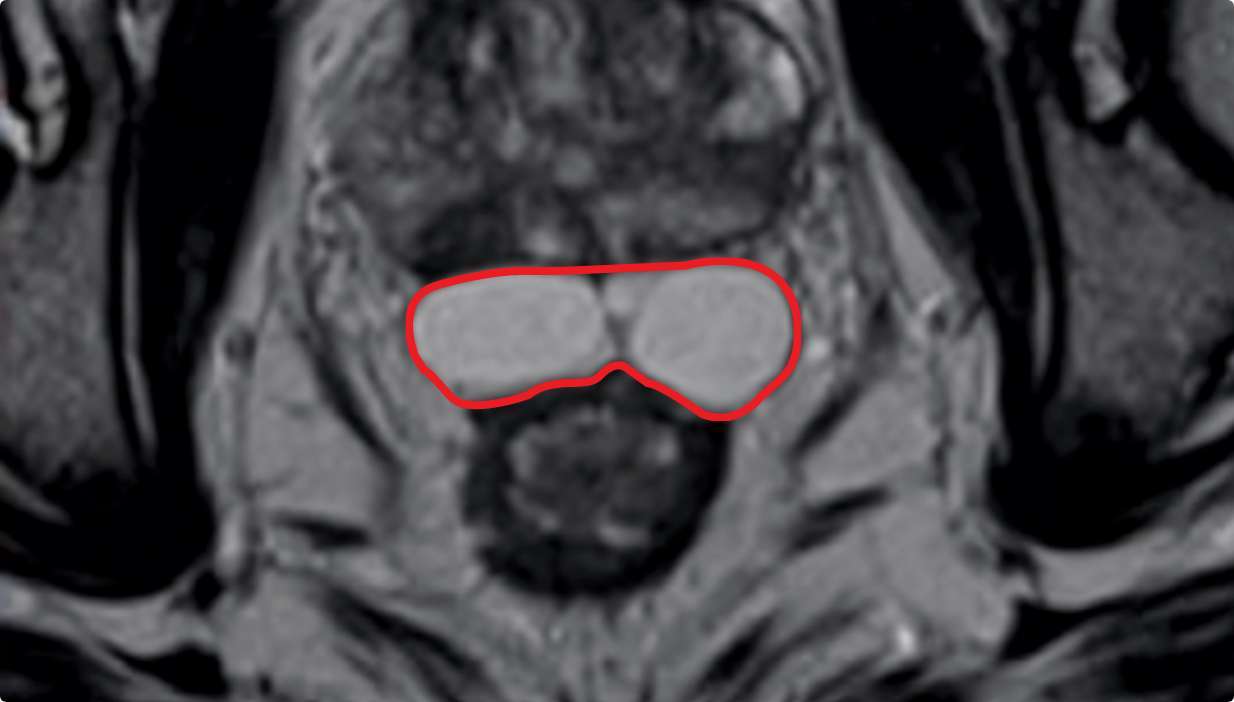

SYMMETRY MATTERS

SYMMETRY

MATTERS